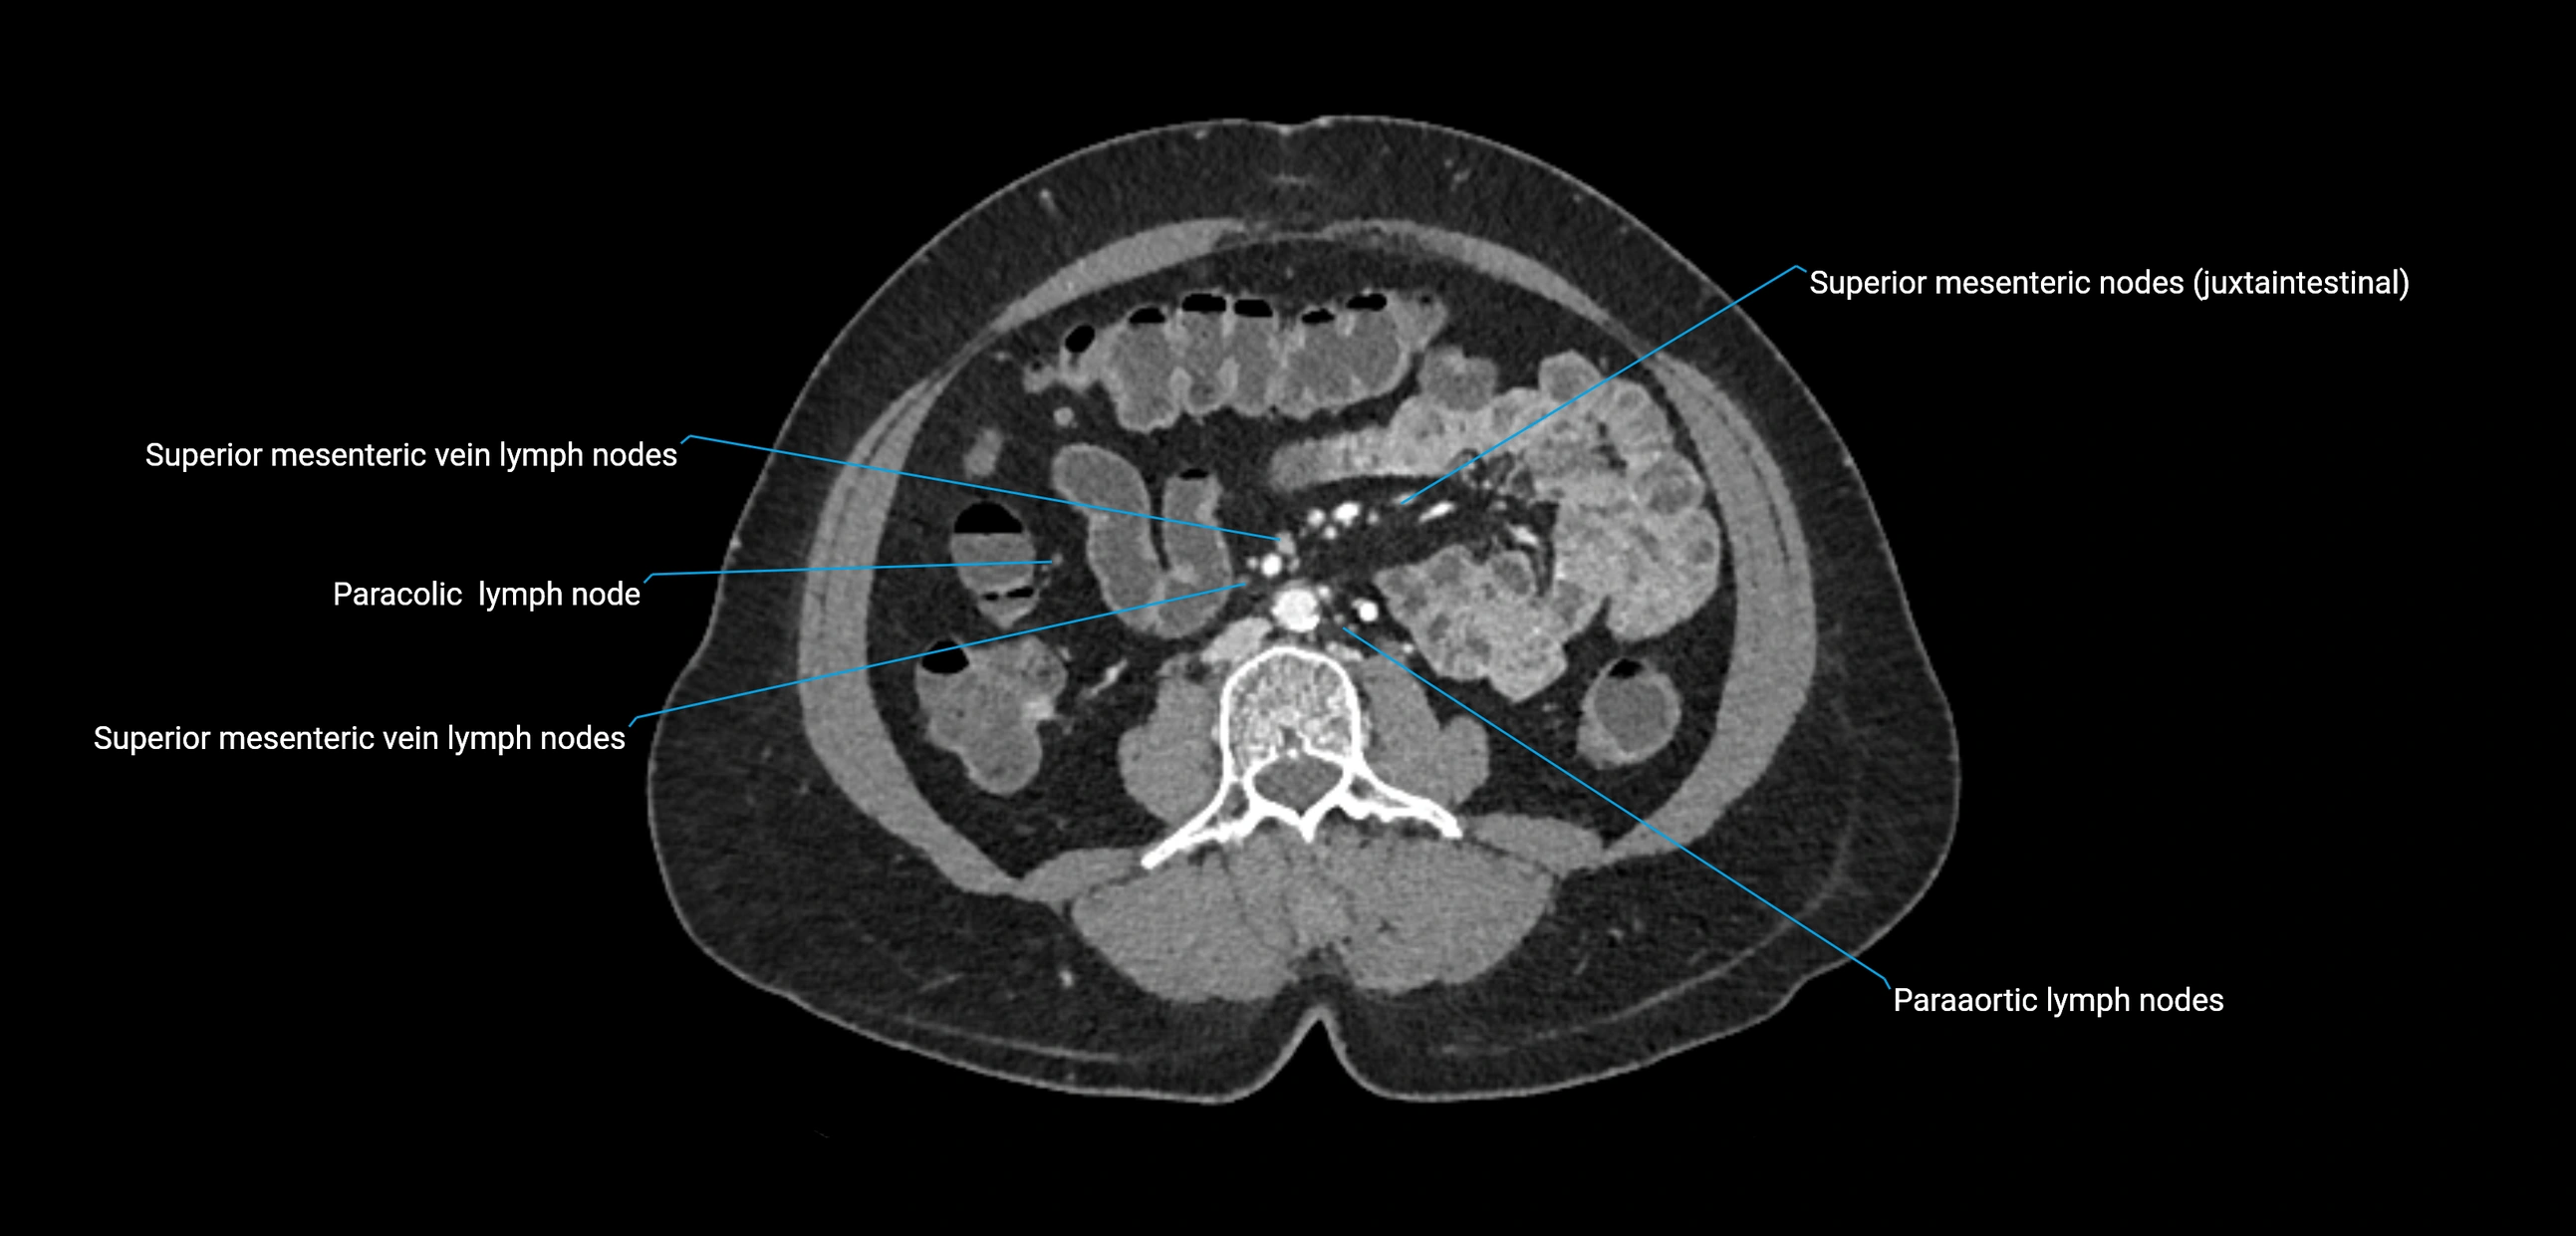

CT Appearance

CT Pre-Contrast:

• Nodes appear as soft-tissue density nodules adjacent to the aorta and IVC

• Calcification may be seen in chronic infections (e.g., tuberculosis)

CT Post-Contrast:

• Normal nodes enhance homogeneously

• Malignant nodes may show heterogeneous enhancement, central necrosis, or conglomerate formation

• Size >1 cm short axis is suspicious, though morphology and distribution are equally important